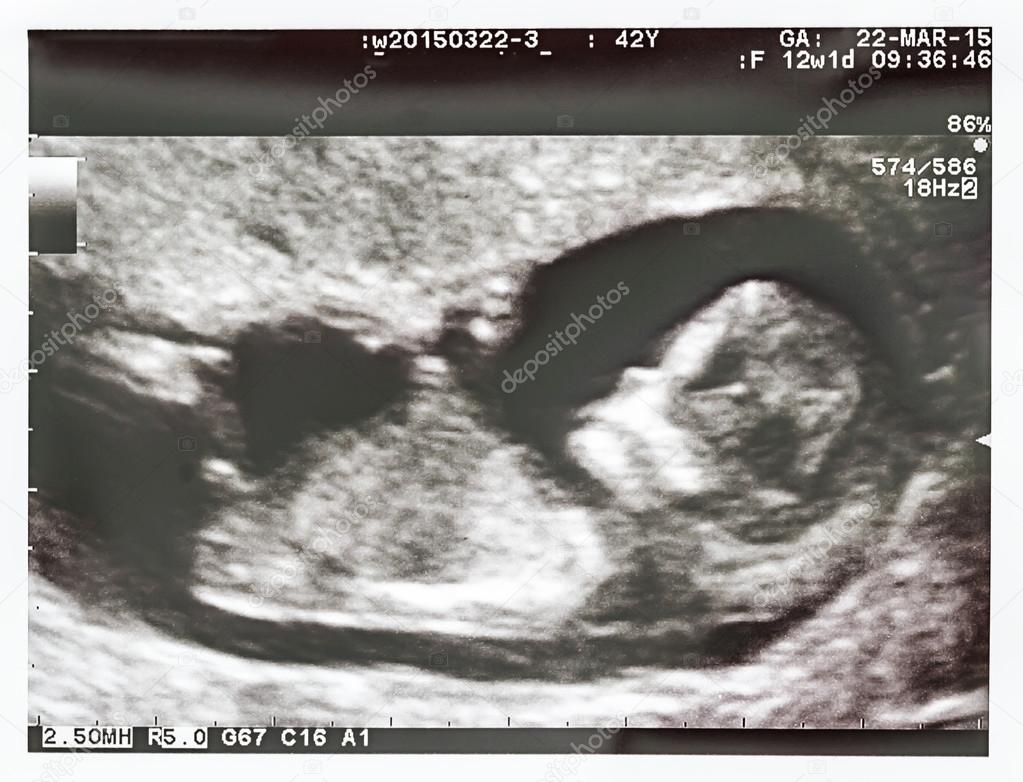

Второе УЗИ плода проводят в конце первого-начале второго триместра (11-13 недель). Здесь оценивают развитие малыша и состояние плаценты. Вместе с этим делают забор крови для анализа на хромосомные патологии.

Для врача первое УЗИ очень важно с медицинской точки зрения. Его проводят (на 11-14 неделях) как часть пренатального генетического скрининга для определения количества плодов, измерения воротниковой зоны и выявления грубых пороков развития. Во время УЗИ можно врач подсчитает, сколько ударов делает сердечко крохи (норма — 130–150 сокращений в минуту), а вы увидите, как он двигает ручками и ножками, сжимает кулачки, поворачивает головку, открывает ротик, глотает и даже пробует сосать свой собственный пальчик. Также на УЗИ фиксируют размеры плода и по ним судят о моменте зачатия.

Первое плановое УЗИ выполняется на 11-13 неделях беременности. В это время можно точно определить многоплодие и некоторые грубые патологии. УЗИ скрининг на первых неделях беременности делают трансвагинально.